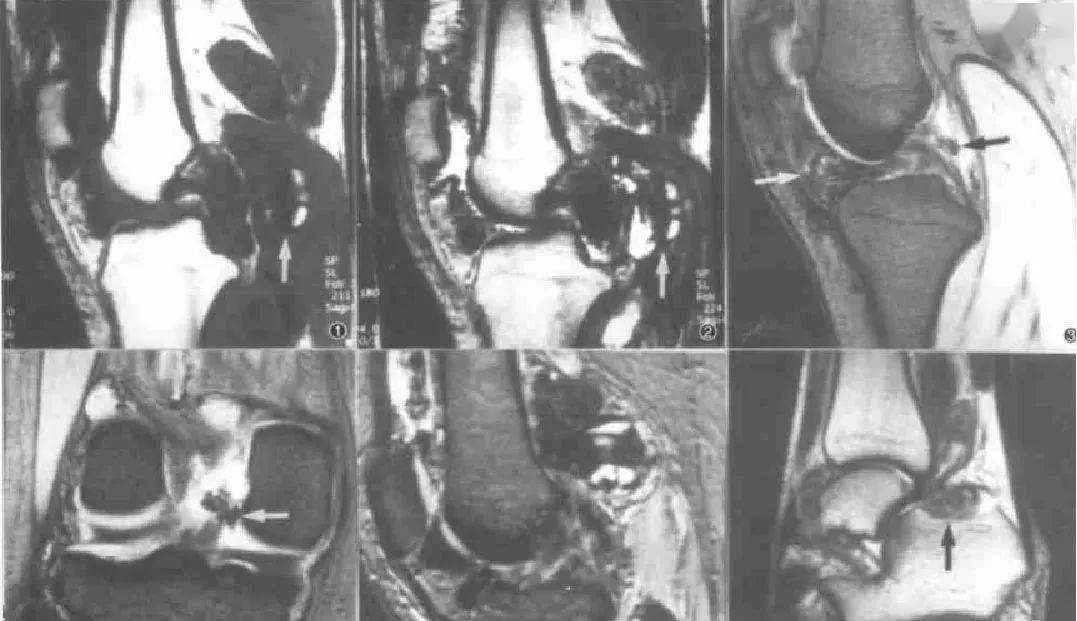

年轻人膝盖疼要不要重视?滑膜炎表现及治疗方法大揭秘!说不定能让你的膝盖“重获新生”。不得不说,中医治疗滑膜炎,真是有一手! 接着讲讲西医治疗方法。西医一般会先让你做个检查,像核磁共振啥的,就像给膝盖做个“高清拍照”,看看里面的情况到底咋样。如果确诊是滑膜炎,轻度的话,医生可能会开点消炎药,就像给膝盖的炎症“泼冷水”...

膝关节滑膜炎具体表现及中西医治疗方法大揭秘!是治疗难治性滑膜炎的标准术式。 目前对于色素沉着绒毛结节性滑膜炎的治疗仍推荐早期外科手术切除,治疗的关键是积极彻底切除病变的滑膜组织,但关节镜具有创伤小、恢复快及并发症少等优势,可能成为PVNS膝关节外科治疗的首选手术方式。 西方医学在治疗这种疾病时,主张采用...